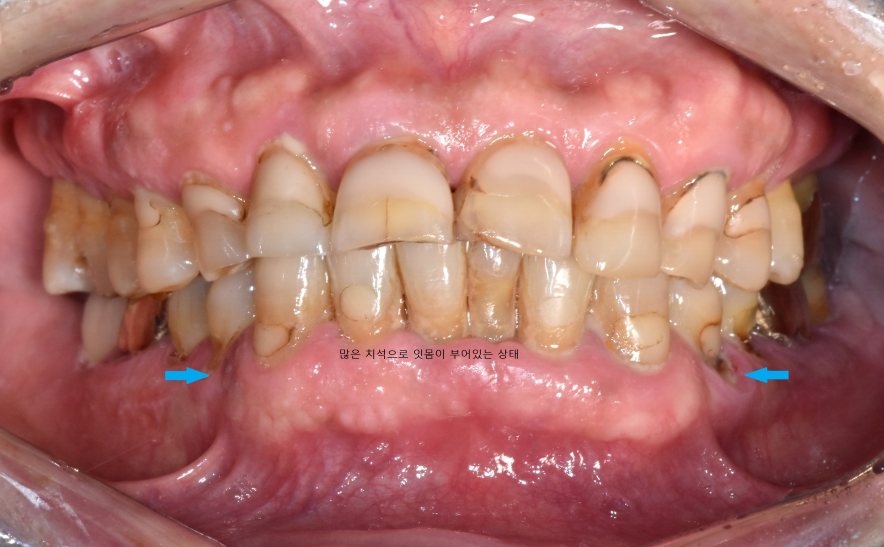

치아 정면사진을 보시면 치아 목부위가 많이 깨져있고

기존에 치아 목부위 치료를 많이 받으셨던걸 보아 저작하는 힘이 강하고

전반적인 구강위생관리가 미흡하고

흡연을 하시는걸 알 수 있었습니다.

먼저, 염증이 심해 잇몸이 붓고 불편하게 하는

오른쪽 위 첫번째 큰 어금니를 발치하면서